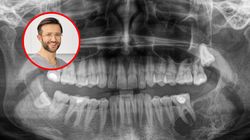

Zrobiłem mostek na implantach, wymaga poprawy, doktor z Bytomia wyjechał za granicę i ślad po nim zaginą. Stomatolodzy nie chcą się podjąć naprawy bez dokumentacji o implantach. Co robić ?

Wskazana konsultacja w specjalistycznym gabinecie implantologicznym.